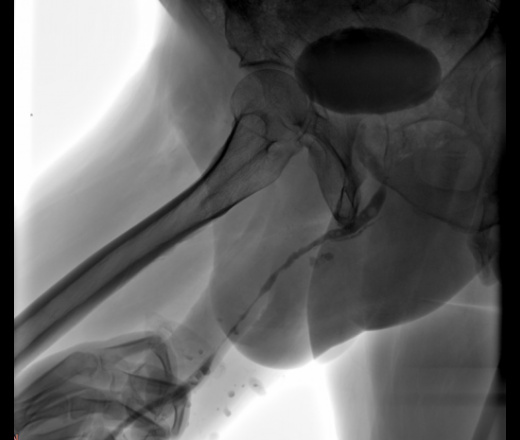

Уретероцистограмма

Мужчина  66 лет. Ищут стриктуру уретры. Уважаемые коллеги, как бы Вы расценили представленную картину?

Смотря что Ваши урологи за стриктуру принимают. По всей длине есть сужения уретры, и простатический отдел. Но, судя по контрасту в мочевом пузыре, все проходимо.

А затек контраста в мембранозной части уретры Вас не заинтересовал?

Наталия Ивановна, а чем обусловлено нарушение целостности стенки уретры?

[чем обусловлено нарушение целостности стенки уретры?

Травм не было. Расценила это так